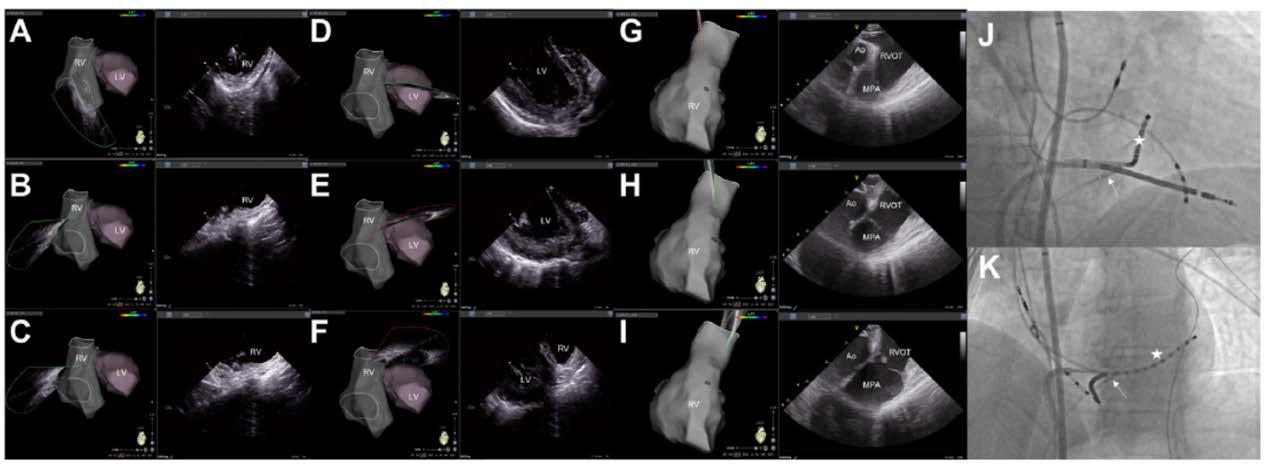

急診室, 3 歲時發作的 12 導程心電圖為 short RP narrow QRS tachycardia ( 圖一、發作時 ) ,因 RP interval 為 120 ms,orthodromic AVRT的可能性較大,retrograde P wave 的型態為I: +/-, II/III/aVF: -, V1: +,delta RP interval of III and V1: 0 ms ,根據 Tai et al. 的研究可以推論可能是 concealed posterior septal accessory pathway(1)。使用 adenosine後,tachycardia可以被矯正回sinus rhythm (圖 二、沒發作時 ) 。自出生後就一直服用 betablocker ,但 仍時常發作,因此在 13 歲時,我們安排了心導管電生 理檢查, RV burst pacing 時最早的 retrograde atrial activation是CS ostium,PAC時會誘發tachycardia (TCL: 446 ms) with the same retrograde atrial activation (concentric) when RV burst pacing (圖三),Ventricular overdrive pacing during tachycardia呈現VAV response with SA-VA of 48 ms and PPI-TCL of 72 ms (圖四),在 VOP 時 fusion beat can reset the next A ( 圖五 ) , Hisrefractory VPC can reset the next A (圖六),在tachycardia 時有出現RBBB pattern也沒有延長TCL (圖七),Antegrade conduction 經由 fast AVN ,綜合以上判斷 orthodromic

AVRT with concealed left posterior septal AP,於是在RV pacing時,我們先從RPS region開始mapping沒有發現有 VA fusion site,然後我們就到retrograde transaortic到LPS region mapping也沒有找到VA fusion的位置,接著我們 的電燒導管在 CS 裡 mapping 時突然掉進 MCV ,這裡發

現有VA fusion (圖八),由於可能很靠近coronary artery

擔心用 RF ablation 會造成 coronary artery stenosis or occlusion(2) ,我們在 ablation 前有先做 coronary angiogram (圖九),coronary artery離VA fusion site都有超 過5 mm,所以我們就使用7F non-irrigated RF catheter在 MCV VA fusion site進行ablation,但是沒有效果,接著 我們做了 CS venogram 發現有一個 CS diverticulum 在 MCV (圖十)(3),我們就把電燒導管移到diverticulum的 neck ( 圖十一 ) ,可以看到 VA fusion ,在 RV pacing 下 50W/50oC 電燒一開始 0.7 秒就 VA block ( 圖十二 ) ,接著 RF booster 120 seconds,post-ablation EP study只有看到 在 V pacing 時有 one fast-slow echo beat , antegrade conduction 有 dual AVNs ,但無法誘發任何 AVNRT or AVRT。病患接受完電燒後,沒有再有心悸的症狀。 (圖一)、發作時12 lead ECG (圖二)、12 lead ECG after adenosine use

(圖八)、VA fusion when tachycardia in MCV

)、冠狀動脈攝影

)、冠狀竇攝影發現

)、VA block within 1 second during RF ablation when RV pacing

(圖九 (圖十一)、X光透視成功電燒的位置在diverticulum neck及3D圖上的成功位置 (圖十二 (圖十 CS diverticulum